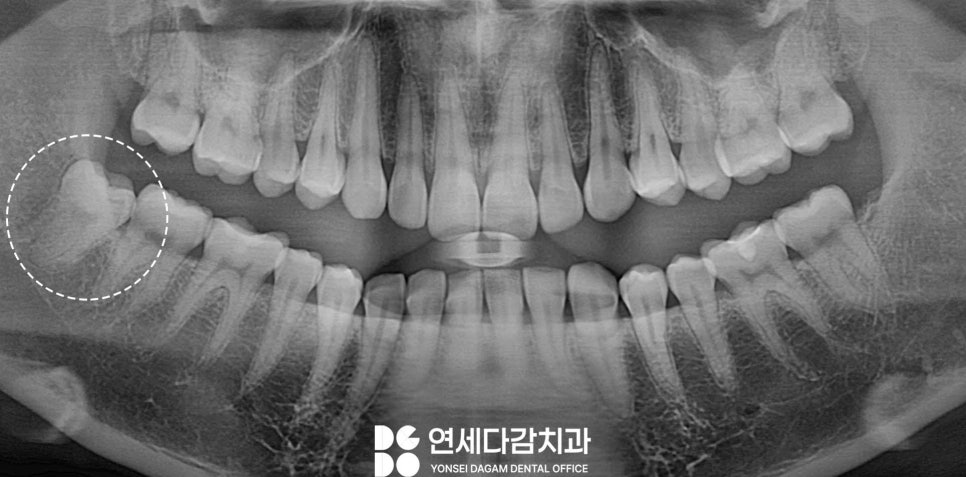

사랑니 발치는 위치와 형태에 따라

난이도가 다양하게 달라집니다

오른쪽 아래 사랑니가

부분 맹출 된 상태에서 음식물이 끼거나

잇몸이 붓는 불편이 생기면

엑스레이를 통해

주변 구조를 먼저 확인하게 됩니다.

사랑니는 끝에 위치해 있어

아래턱에서 지나가는 주요 신경인

하치조신경 같은 해부학적 구조물과

가깝게 위치해 있는 경우가 많습니다.

그렇기 때문에 특히 하악의 경우는

CT를 통해 신경과의 거리를

입체적인 3차원 구조로

살펴보는 것이 필요합니다.

CT로 확인했을 때 사랑니의 뿌리가

아래턱뼈의 겉면인 치밀골 쪽으로

살짝 박혀있는 모습을 보일 수 있습니다.